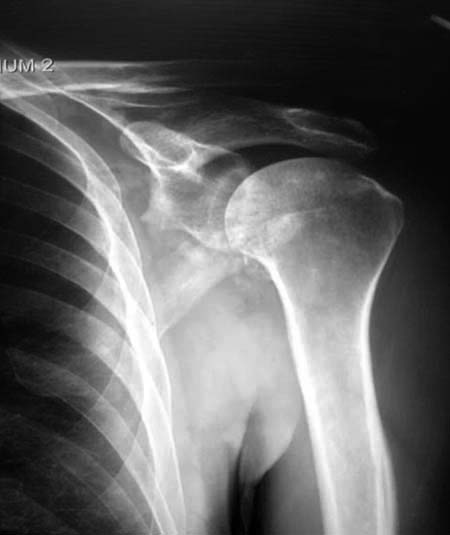

Данный перелом относится к перелому тело лопатки и несмотря на наслоение, где лопатка покрывает грудную клетку, но можно увидеть три большие фрагмента, которые находятся в разных плоскостях. Суставная поверхность расположена намного медиальнее, что нарушает бланс мышц, которая в последующем может привести к ограничению движения верхного пояса. Расположение суставной поверхности нуждается в уточнении дополнительными исследованиями, включая КТ и стандартные снимки плеча.!

Здесь пример, стандартные снимки: плечо и лопатка прямой снимок, аксиллярный и косой снимки (Y-view) и фиксация пластинами по краям, где имеется более твердая кость. Специальные пластины, хотя любая 2.7 или 3.5 мм тубулярная пластина подойдут для фиксации перелома. Риск операции - это повреждение нерва во время доступа и ре-фиксация ротаторной манжетки если потребуется широкий доступ!